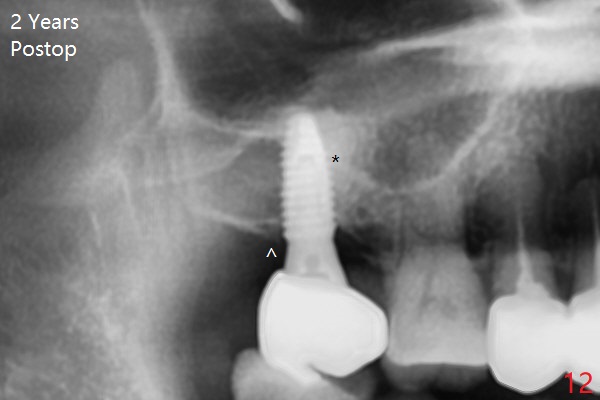

After extraction of the 3rd molar with mesial periodontal defect, osteotomy for 2nd molar implant is initiated in the mesial slope of the 3rd molar socket (Fig.1 red dashed line). When osteotomy is finished with IS drills and sinus lift with Magic Sinus Lifter (S-reamer with 11 mm stopper being short), a 4x10 mm dummy implant is placed with ~ 4 implant thread exposure (Fig.3). Following use of Lindamann bur to move osteotomy mesial and larger drill, a 4.5x10 mm implant is placed with 5-7 implant threads exposed distally (Fig.4,7 (~ 50 Ncm)). The bucco(B)-palatal(P) extent of the implant thread exposure is larger (Fig.5) than that associated with the 4 mm dummy implant (data not shown). The exposed implant surface is covered with Vera Graft (Fig.7*), Collagen plug and an immediate provisional after adjustment of abutment height (Fig.6,7). The bone density distal to the implant is low 3 months postop (Fig.8,9 CBCT) and 3.5 months postop (Fig.10,11). The permanent crown is cemented nearly 4 months postop. The distal cortical bone contacts the implant (Fig.12 ^), while the mesial bone increases in density (*) 2 years postop.